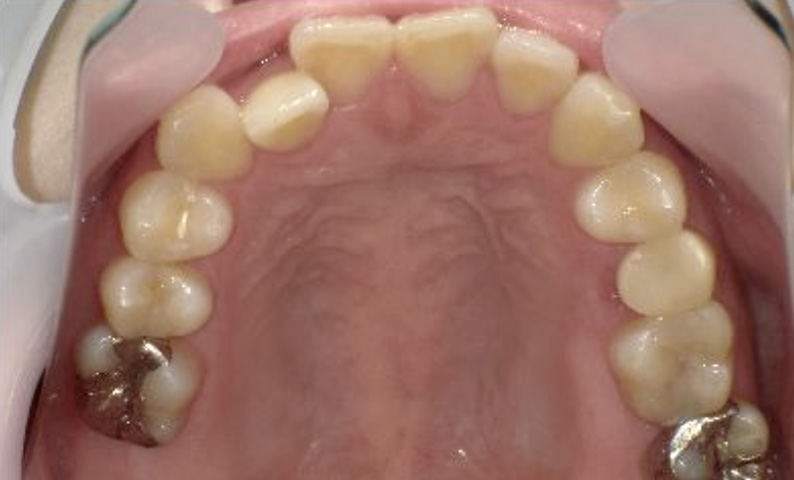

症例_024 上顎だけの部分矯正

治療期間:7ヶ月金額:30万円+税女性前歯のガタガタ上の前歯だけ

| Before | After |

|---|---|

|